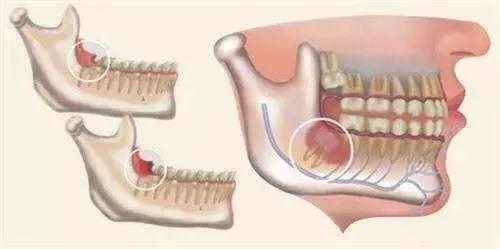

·根尖周囊肿:根尖肉芽肿受到炎症的长时间刺激,会使牙周膜内部的上皮残余增生,增生后上皮组织病变液化就会一连 导致周围组织一直 渗透 液体,形成囊肿。

·始基囊肿:青少年乳恒牙患牙期发生的囊肿许多是始基囊肿;上皮组织在受到炎症或外伤刺激时,成釉器星网状层病变会渗透 液体且无法倾轧 ,逐步形成单囊或多囊。

·滤泡囊肿:病发部位与年岁 有关,与始基囊肿类似也多发于替牙期;牙冠或者牙根形成之后所余釉上皮渗透 液体,形成囊肿,囊肿内可能会含有一颗或多颗牙胚,故也被称为含牙囊肿。

·角化囊肿 :多发病与20至40岁青壮年时期,泉源 于原始的牙板加入或者是牙胚,以是 大部门患者牙齿排序不齐,有缺牙少牙的症状;囊肿生长缓慢,与其他囊内清亮液体差异的是,角化囊肿积液泛起白色或者黄色。